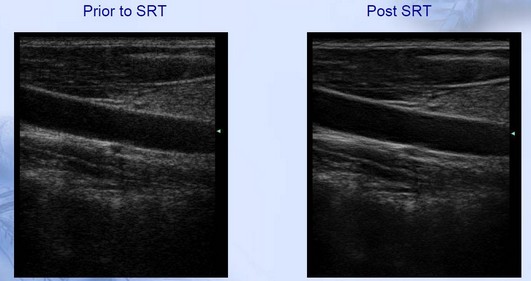

Imagenes con tecnología SRT(Speckle Reduction Technology):

• Suprimir los ruidos de echos

• Minimizar los granos de imagen

• Caracterización de tejido automatico

• Mejora la resolución de imagen

• Purifica el contorno de tejido

• Ayuda indentificación temprana de tejido con estructura de lesion